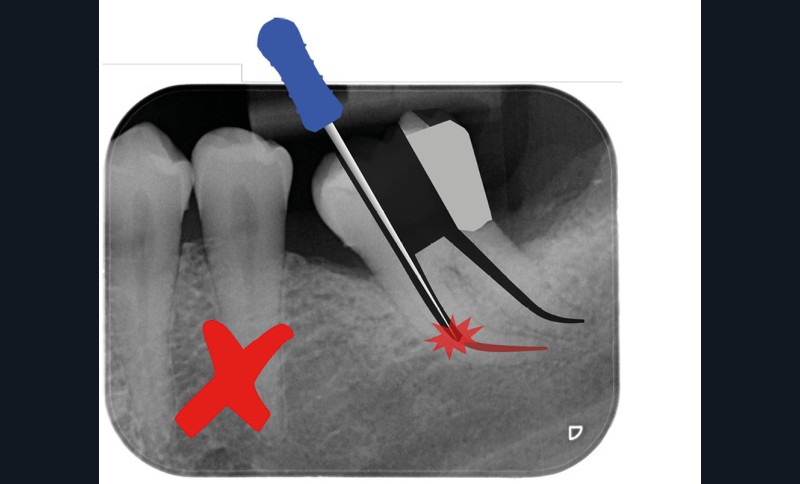

Trop petite

Une cavité d’accès trop petite [2] optimiserait le pronostic biomécanique (préservation dentaire maximale) mais pourrait compromettre le pronostic endodontique : mauvaise lecture de l’anatomie, instrumentation partielle, non ergonomique et avec risque de fracture, défaut de nettoyage des parois canalaires [3], irrigation inadéquate, difficulté d’obturation canalaire, voire d’obturation coronaire. Ce sera le cas des cavités d’accès « Ninja » [4] ou ultraconservatrice (fig. 1), des cavités d’accès « Truss » [5] (fig. 2), des cavités d’accès dites « opportunistes » [6] (fig. 3).